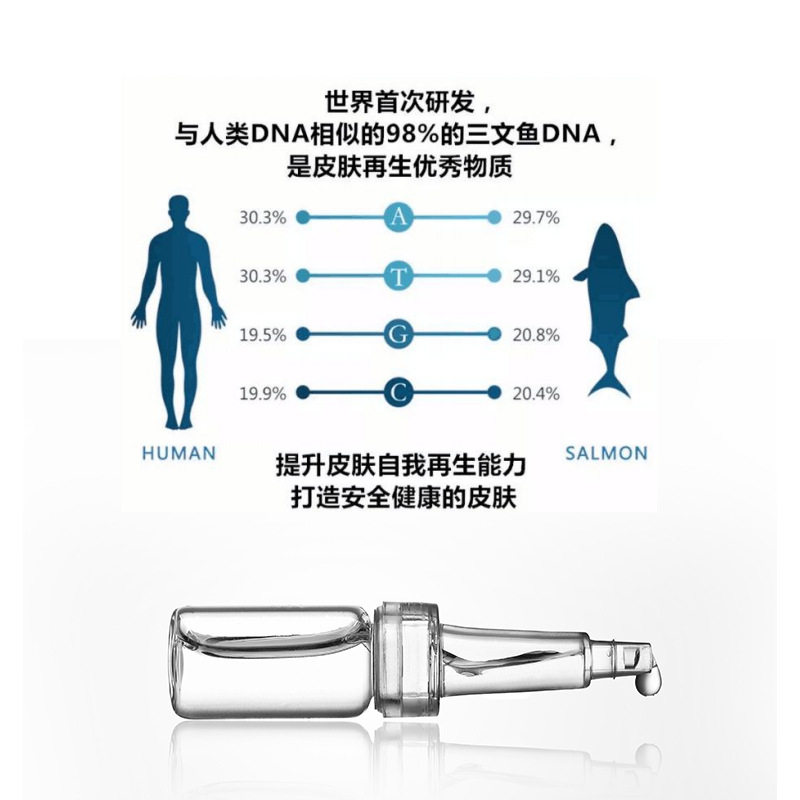

Pdrn Salmon Essence Dna Sodium Lightens Wrinkles, Brightens Skin, Revitalizes Skin Care, Classy Hydrating Set, Exclusively for Beauty Salons

| Product name | Salmon water light essence |